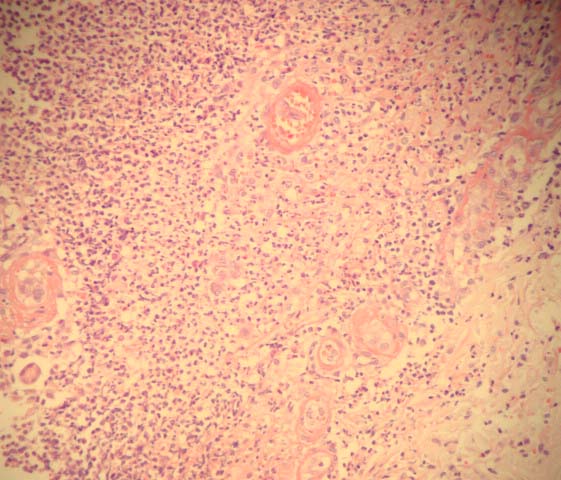

O Pioderma Gangrenoso (PG) é uma dermatose inflamatória neutrofílica rara, de etiologia desconhecida, associada a doenças sistêmicas em 50% dos casos. No presente trabalho, faz-se uma breve revisão sobre este distúrbio, demonstrando as repercussões sobre a Cirurgia Plástica. Relata-se o caso de uma paciente de 40 anos, submetida a mamoplastia redutora e abdominoplastia, com apresentação de lesões típicas de PG nas cicatrizes cirúrgicas no 6º dia pós-operatório e excelente resposta à terapêutica clínica. Discutem-se, ainda, as formas clínicas da doença, as bases diagnósticas e o tratamento atualmente disponível.Downloads